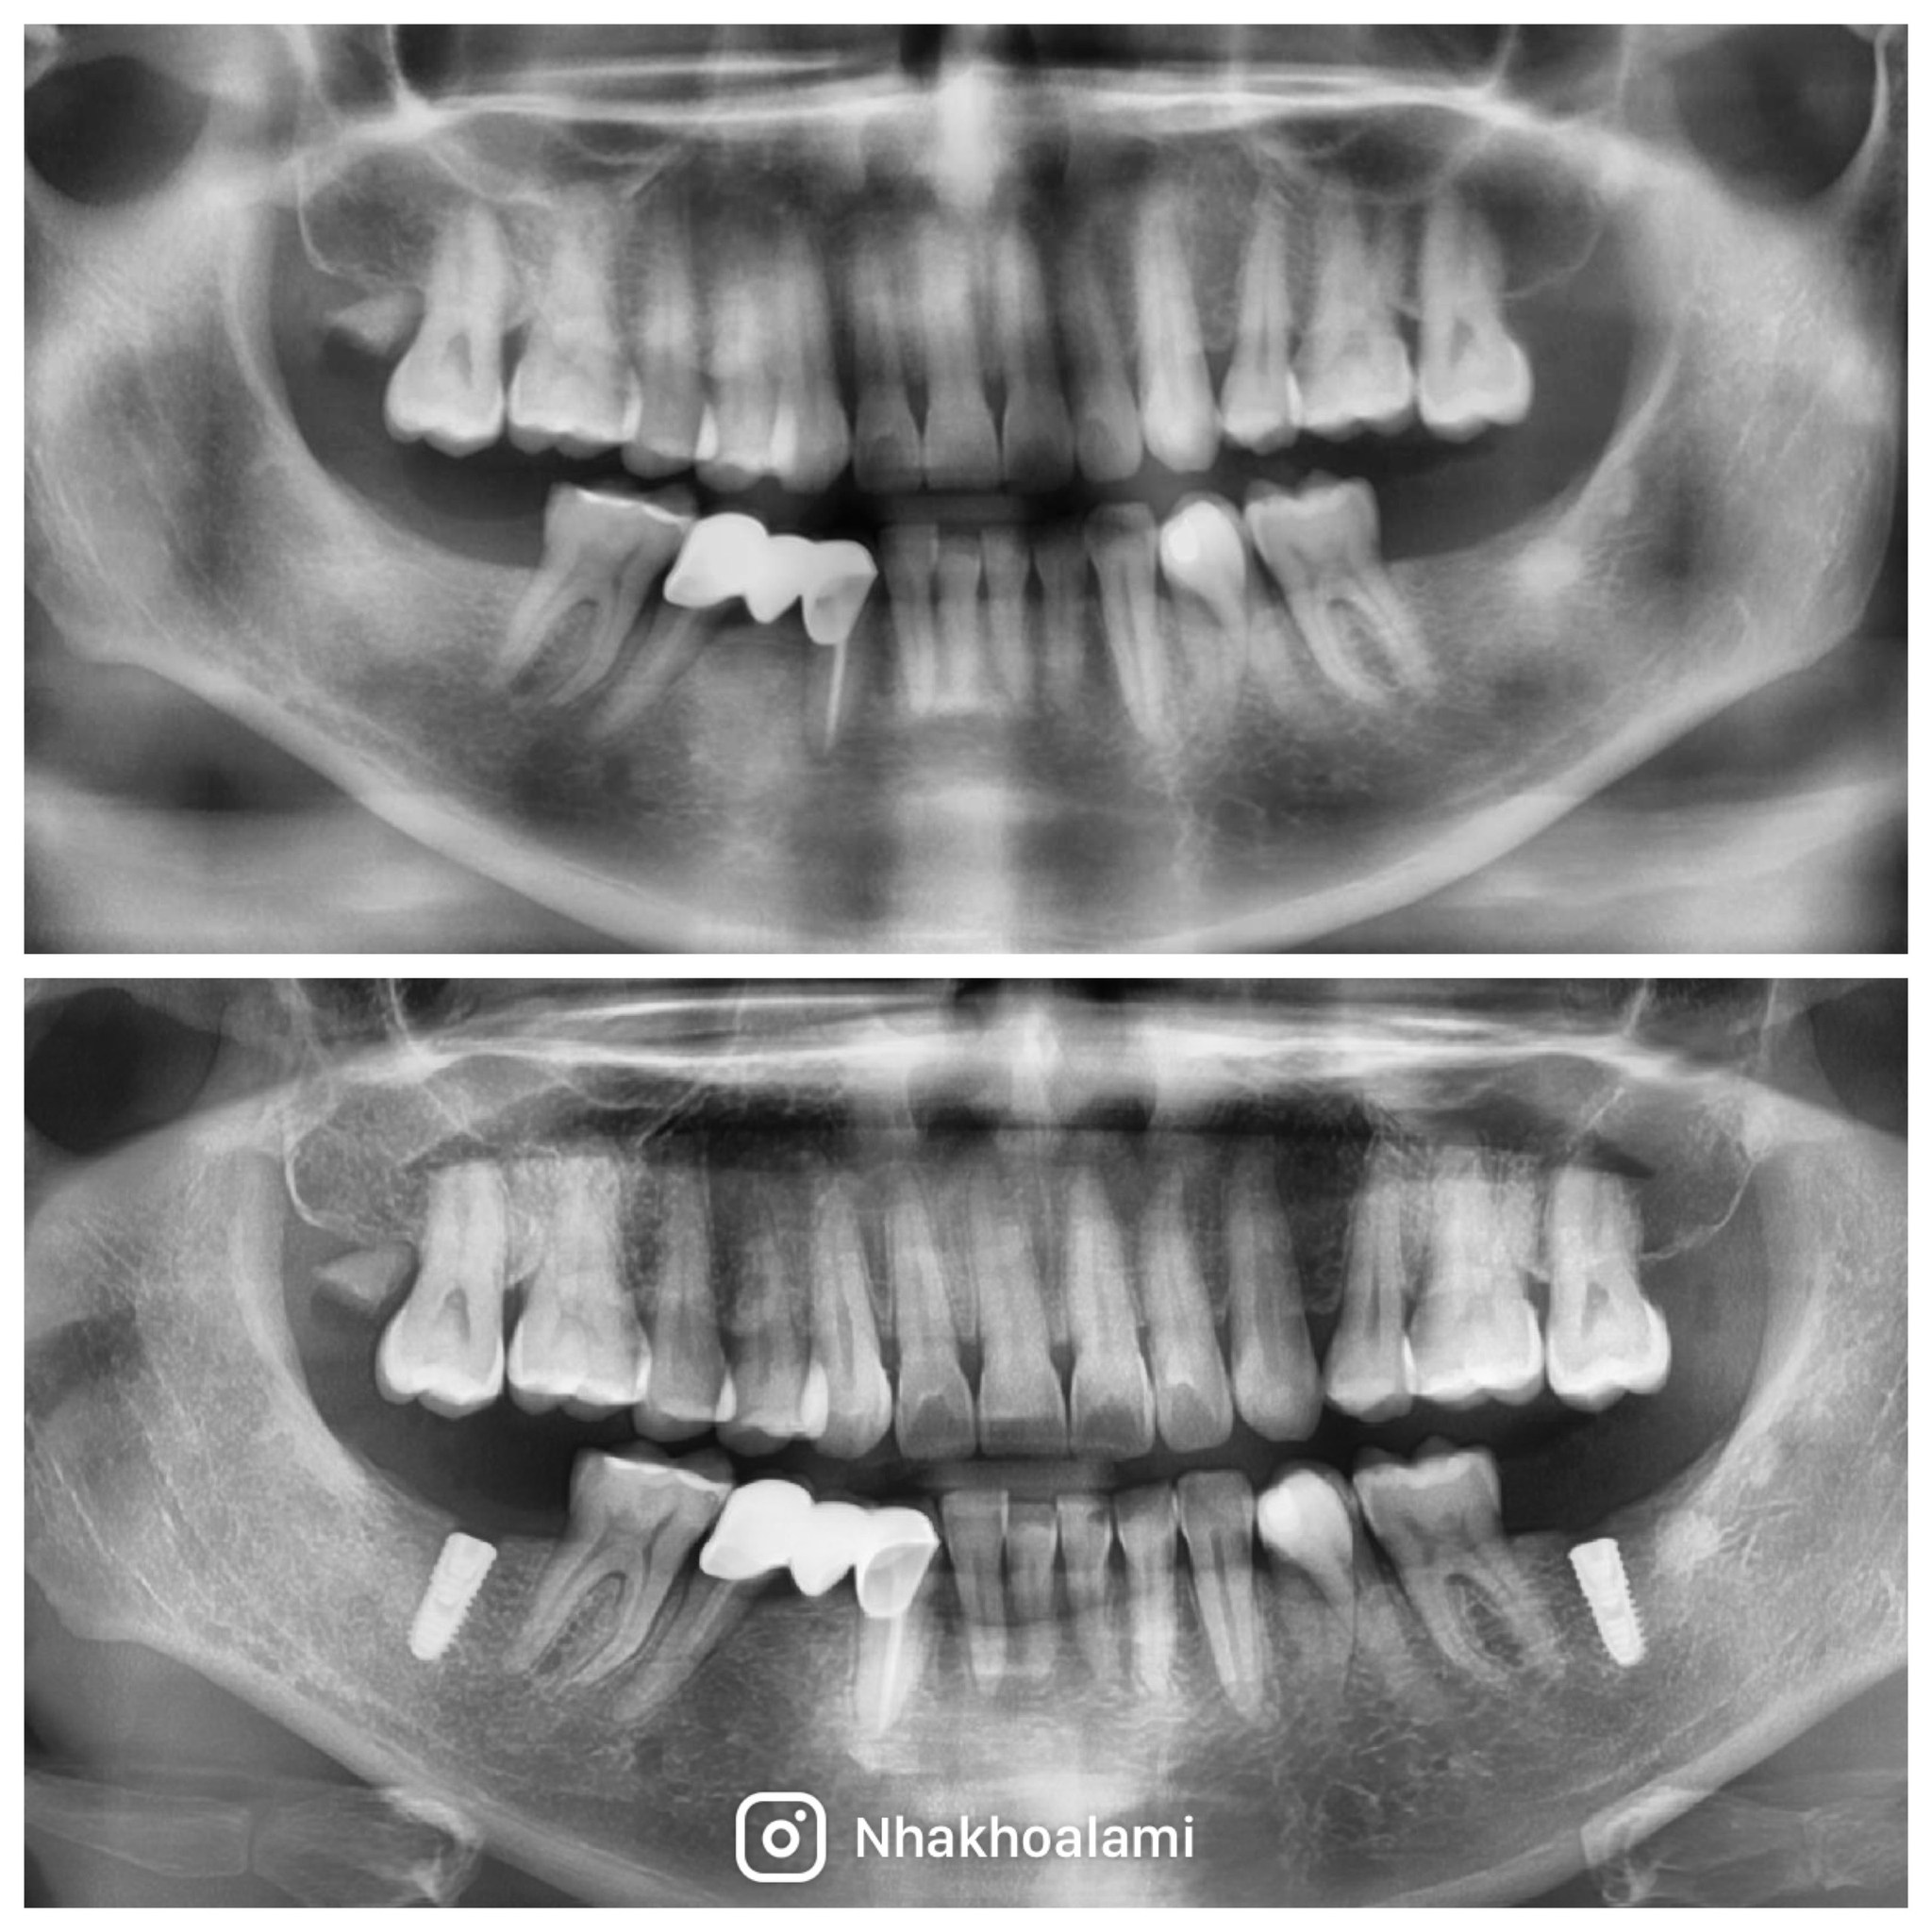

Case Khách hàng: 18/09/2024 - Case đặt 5 trụ Implant Hiossen được thực hiện bởi Bác sĩ CKI Trần Hữu Duyệt.